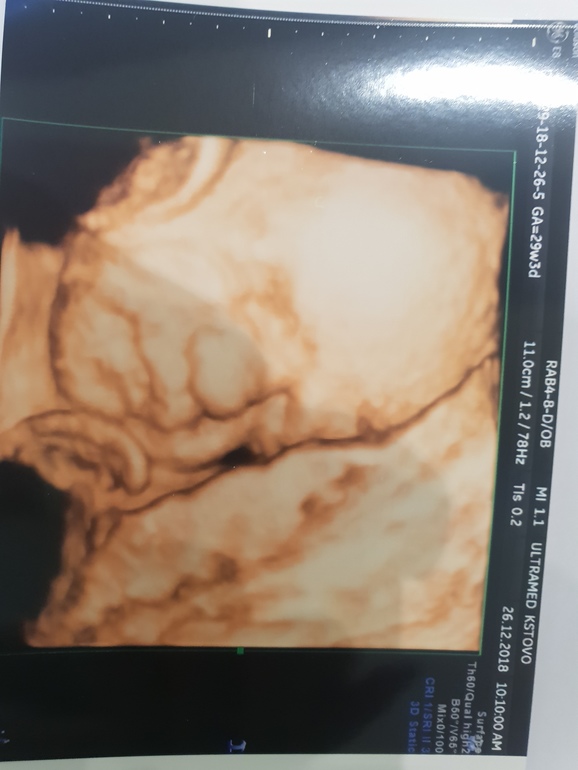

Узи 29недель, плацента 2й степени....чем может грозить????

26.12.2018